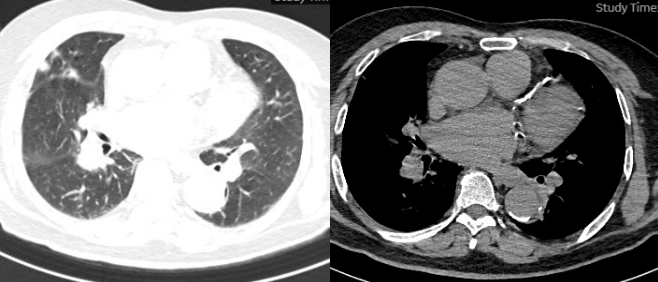

5月3日胸片:双肺渗出(图7)

7  患者胸片(2025-05-03)